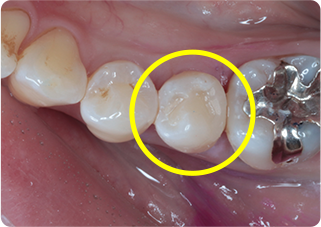

精密根管治療②

術前

術後

| 主訴 | 奥歯で噛むと痛い |

| 治療期間/回数 | 1ヵ月、3回 |

| 価格(税込) | 88,000円(税込) |

| リスク・副作用 | 病変再発、歯根破折の可能性 |

| ポイント | う蝕検知液を用い、むし歯の取り残しが無いようにし、ラバーダム防湿を行い、無菌的に根管治療を行った。根管充填材は、殺菌作用の強い保険適応外のMTAセメントを使用した。 |